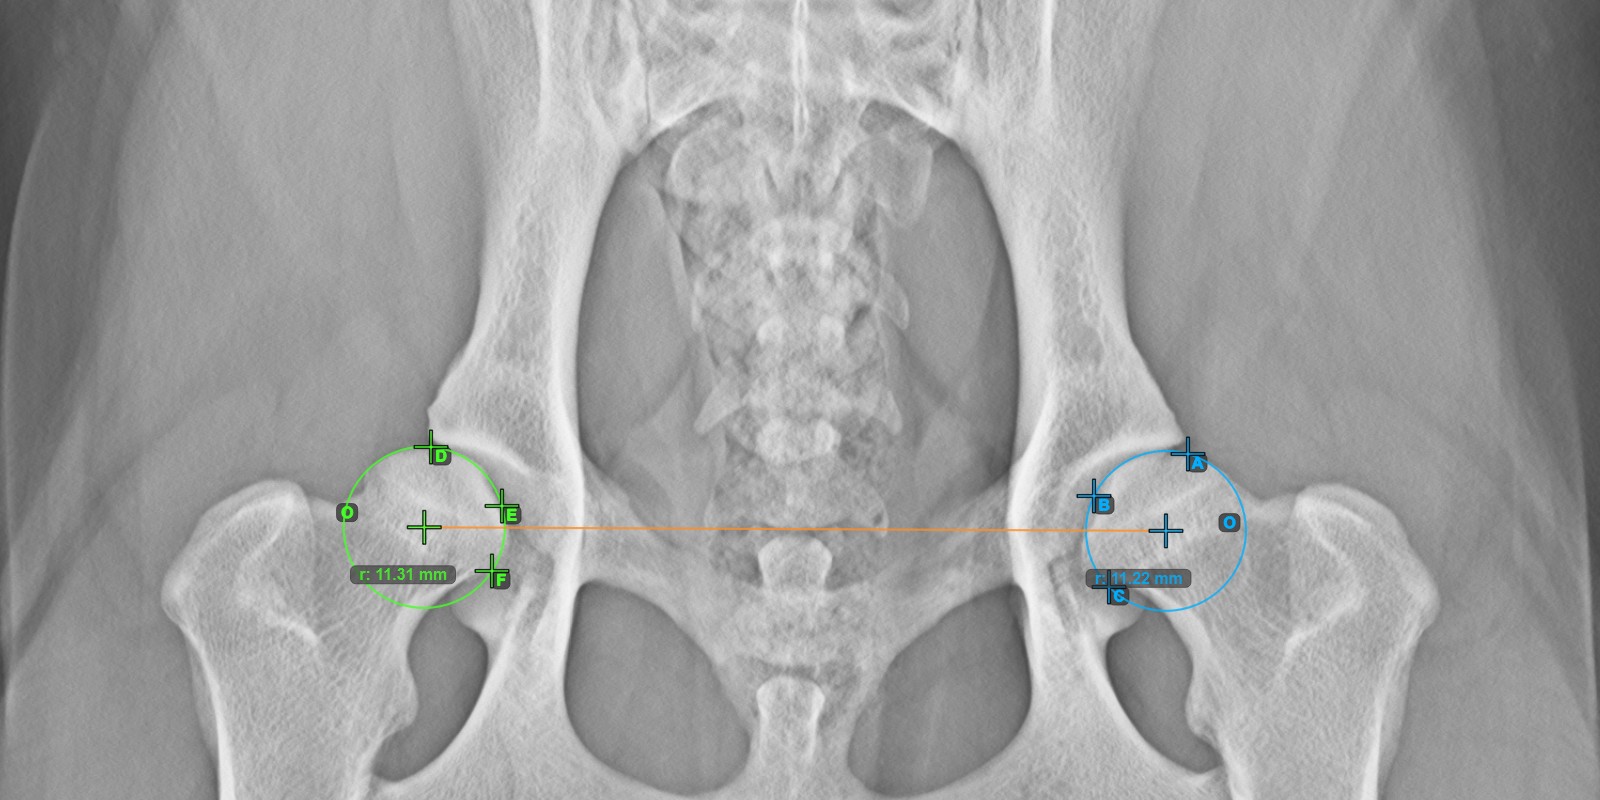

Das Bild unten zeigt die typische Platzierung der Linie und die berechnete Norberg-Winkel-Messung.

Die gezeichnete Linie muss eine Tangente an der effektiven Kante des rechten Acetabulumknochens sein. Der Wert und der Bogen des Winkels werden automatisch berechnet.

Setzen Sie einen Punkt in der Nähe des rechten Caput Femoris und ziehen Sie ihn entlang der effektiven Kante des rechten Acetabulumknochens, um die Schenkelseite des rechten Norberg-Winkels zu bilden.